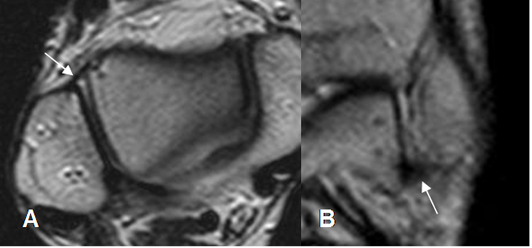

Fig 12. Ligamento peroneocalcáneo normal.

A: RM axial y B: RM coronal en T2.